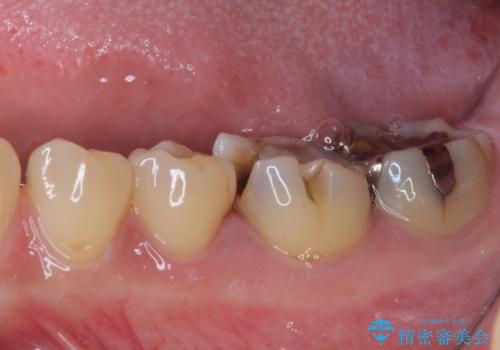

奥歯は虫歯が放置されていましたが、特に症状はなく歯髄の状態も正常でした。

前歯、奥歯ともにオールセラミッククラウンやセラミックインレーにて治療を行うこととしました。